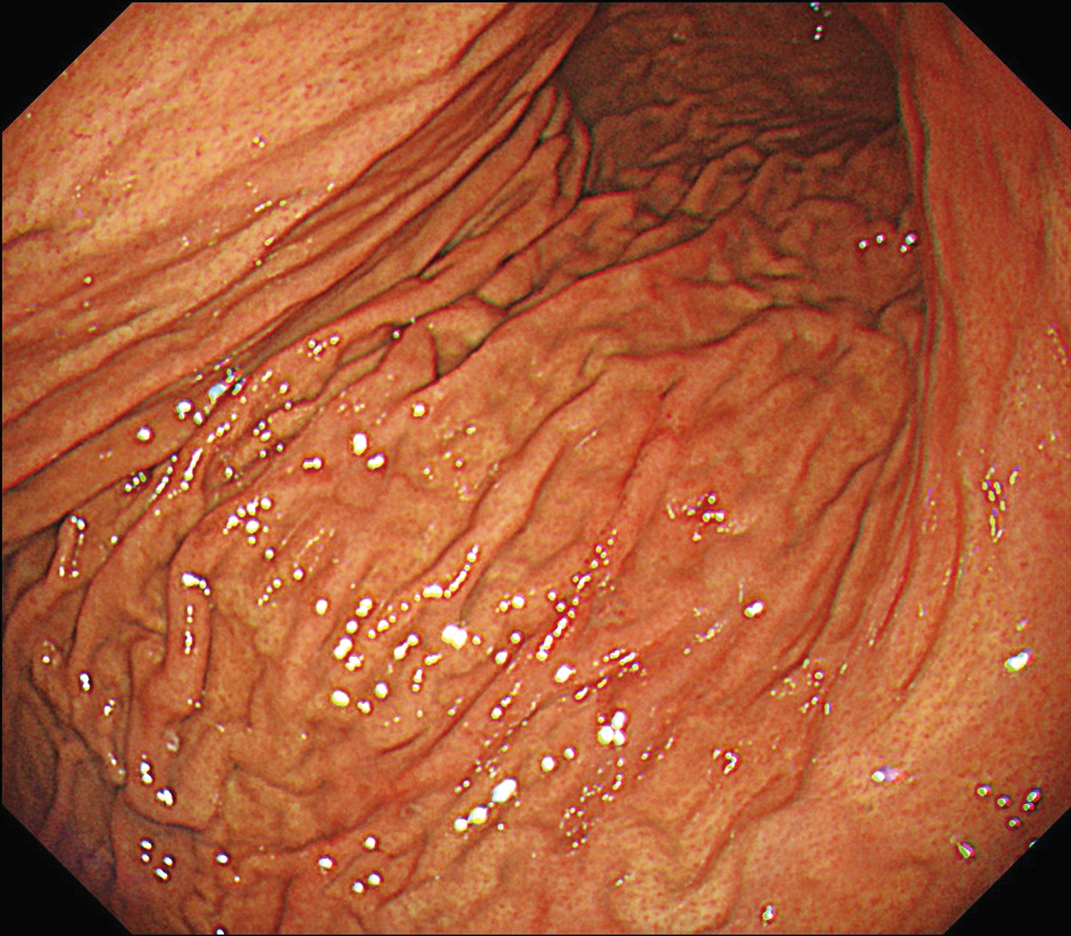

EVIS X1×GIF-1200N 症例画像

胃体上部大弯